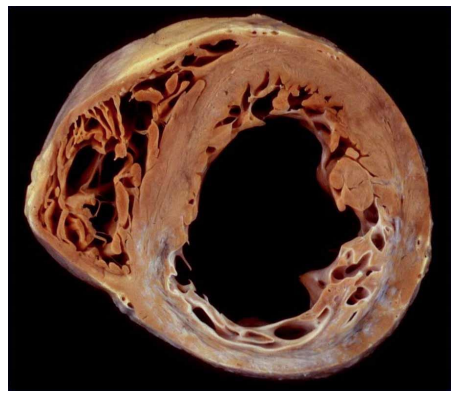

A 75-year-old woman is undergoing intestinal surgery for colon cancer. She recalls having a “heart attack” several decades ago but is unclear on the details. She dies suddenly on post-op day 3. An autopsy is performed, and cross sections through the two ventricles are examined.

A. What is the diagnosis?

B. What 3 gross findings are the basis of this diagnosis?

C. Name 7 potential consequences or outcomes:

D. What 2 other cardiac abnormalities are likely present?

A. remote MI

B. fibrosis - old MI –> thinnning of wall, dilation

C. arrhythmia, systolic dysfunction, aneurysm, chronic regurgitation –> dilated LA –> thromus –> emboli, sudden death

D. coronary atherosclerosis, mitral insufficiency